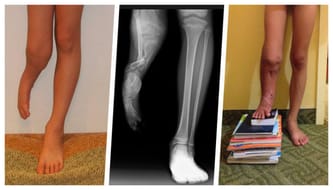

Byliśmy w Stanach już dwukrotnie. Za obie operacje zapłacił NFZ, a dr Paley wydłużył łącznie o 16 cm kość piszczelową, poprawił funkcjonalność kolana oraz kostki, jak również przesunął kość strzałkową w miejsce, gdzie powinna się znajdować. Drugi wyjazd do USA nie byłby możliwy bez wsparcia darczyńców (otwiera nową kartę), którzy pomogli nam opłacić wielomiesięczny pobyt za oceanem.

Od tamtego wyjazdu nóżka Alana, której bez naszej determinacji dawno już by nie miał, urosła razem z nim. Stała się niemal dorosłą nogą ale wciąż jednak jest 20 cm krótsza od swojej zdrowej siostry. Dr Paley, jako jedyny na świecie dał nam nadzieję na 100% wyleczenie, czyli dwie równe nogi. Mój syn będzie mógł w przyszłości funkcjonować jak jego rówieśnicy, ale potrzebna jest kolejna operacja w 2019 roku. Nie możemy zatrzymać się w połowie drogi. Syn cały czas rośnie i musimy kontynuować leczenie. Niestety, tu zaczynają się strome schody…